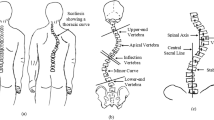

The classification by King is still the most widely used technique in surgical planning. It defines 5 thoracic curve types and an identical group called miscellaneous. The King classification relies on subjective identification and measurement of radiographic features including the apical and end vertebra of the curve, vertebral end plate and origin of alignment of the central sacral line(CSL). The King’s classification definition follows as below (refer Fig. 1).

King Type I: Shows an S-shaped curve crossing the mid line of the thoracic and lumbar curves. The lumbar curve is larger and more rigid than the thoracic curve.

King Type II: Shows an S-shaped curve where both the thoracic major curve and the lumbar minor curve cross over the mid line. The thoracic curve is the largest curve.

King Type III: Shows a thoracic curve where the lumbar curve does not cross the mid line.

King Type IV: Shows a long thoracic curve where the 5th lumbar vertebra is centered over the sacrum, but the 4th lumbar vertebra is already angled in the direction of the curve.

King Type V: Shows a thoracic double curve where the 1st thoracic vertebra angles into the convexity of the upper curve.